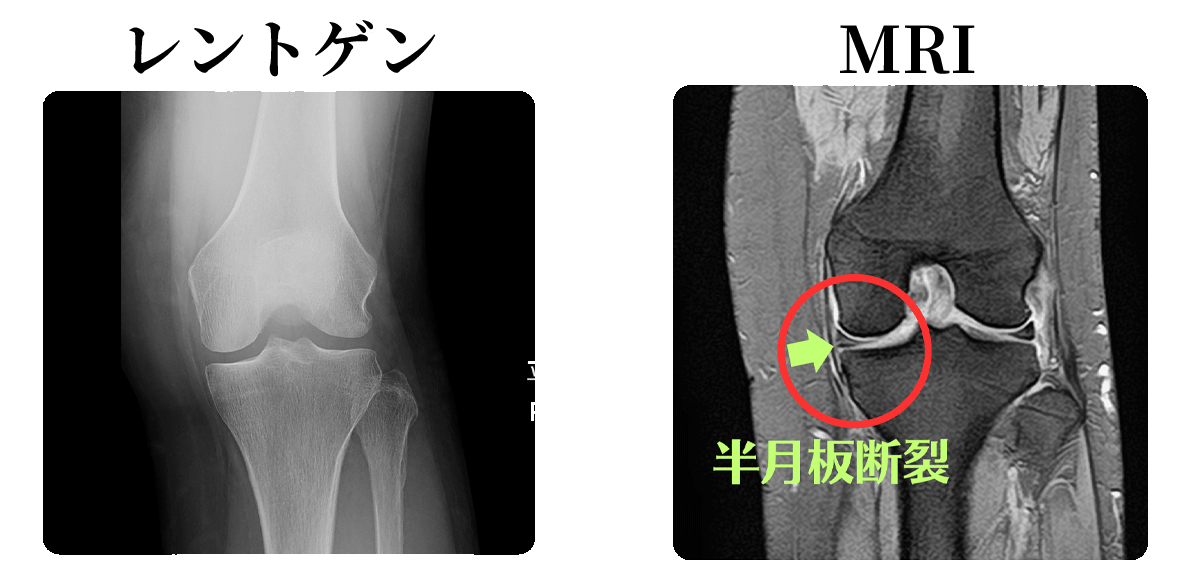

レントゲン検査では捉えにくい、筋肉、靭帯、軟骨といった軟部組織の異常を、より鮮明な画像で確認できるようになりました。

レントゲン検査は骨の状態を把握するのに優れていますが、靭帯や半月板、神経、筋肉などの軟部組織の損傷は映りにくいという特徴があります。

MRI検査では、こうしたレントゲンでは見えない部分を詳細に画像化し、痛みの真の原因を特定します。

軟部組織がはっきり見える!

筋肉、腱、靭帯、軟骨、脂肪組織などの「軟部組織」の状態を非常に鮮明に画像化できるという大きな特徴があります。

レントゲンやCTでは骨が主に描出されるため、骨以外の組織の異常を見逃す可能性がありますが、MRIでは組織のわずかなコントラストの違いを捉えられるため、軟部組織の病変や損傷の診断に非常に有効です。